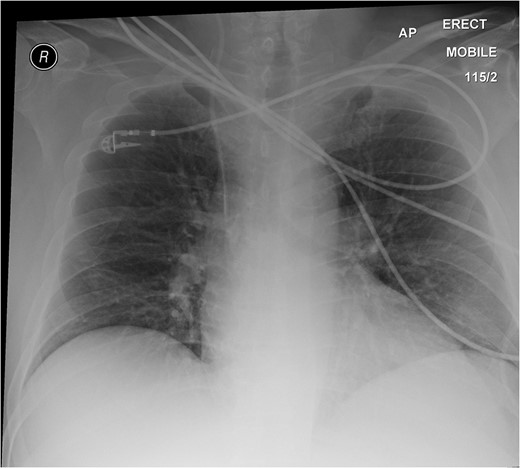

On physical examination, he was pyrexial at 38.4°C, tachycardic with a pulse rate of 120 beats per minute, tachypnoeic at a respiratory rate of 20 per minute and a blood pressure of 130/70 mmHg. Clinically, he appeared flushed and in pain. His abdomen was not distended but tender and guarding in the right upper and lower quadrants. Right flank tenderness was also elicited. There were no hernias and his chest was clear.